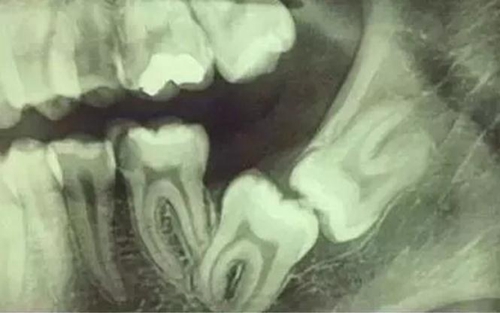

拍片是為了了解智齒周圍情況,也是為了了解智齒結(jié)構(gòu),牙根結(jié)構(gòu)千變?nèi)f化,有可能是融合成一個(gè)根,也可能是八爪根。不同牙根不同位置及方向,只有通過拍片來確認(rèn)。

通過拍片可以了解牙齒本身:生長方向,牙根數(shù)目,牙根是否彎曲,膨大等。

與重要解剖結(jié)構(gòu)的位置關(guān)系:如上頜磨牙與上頜竇的關(guān)系;下頜磨牙與下頜神經(jīng)管的關(guān)系;兒童在混合牙列期恒牙與乳牙胚的關(guān)系等。可以減少拔牙的風(fēng)險(xiǎn)。